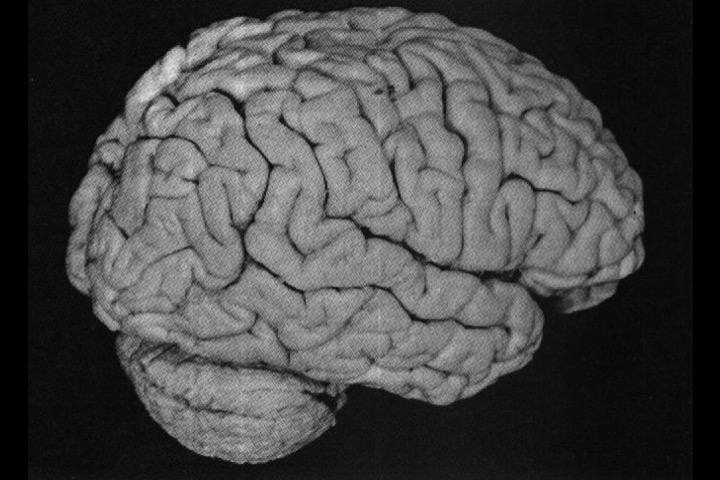

O Prof. Emérito da UFRJ Dr. Adalmir Morterá Dantas está disponibilizando através de nosso website e de nosso canal youtube (cursobom) o Museu de Neuroanatomia, no intuito de promover esta área de conhecimento junto aos estudantes de Medicina.

As figuras são apresentadas em 4 vídeos no youtube e podem ser obtidas via download clicando-se na figura em questão.